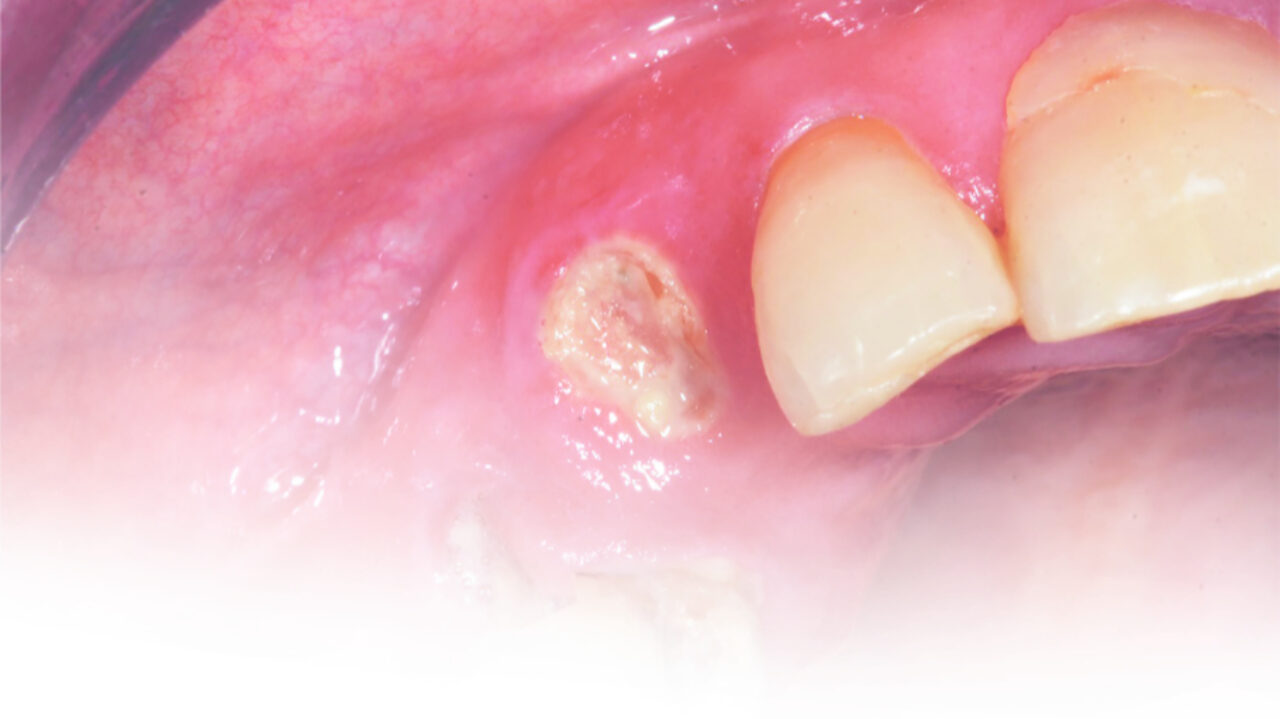

Το Biodentine™, έχει δείξει ένα δυνατό ιστορικό κλινικών επιτυχών. Το Biodentine ™ (Septodont) είναι ένα υλικό πυριτικού ασβεστίου που περιέχει πυριτικό τριασβέστιο και διασβέστιο, οξείδιο του αργιλίου και χλωριούχο ασβέστιο. Εμφανίζει μια μεγάλη ποικιλία χρήσεων και στη νεογιλή και τη μόνιμη οδοντοφυΐα. Μπορεί να χρησιμοποιηθεί για την έμμεση και άμεση θεραπεία του πολφού, σε πολφοτομές (καθολικές και μερικώς), ακρορριζικές φραγές (apexification), επιδιορθώσεις διατρήσεων και εμφράξεις ριζικού σωλήνα.

Διαβάστε ολόκληρο το άρθρο για τη κλινική χρήση του Biodentine™ σε πολφοτομές στα πρόσθια και οπίσθια νεογιλά δόντια παρακάτω.